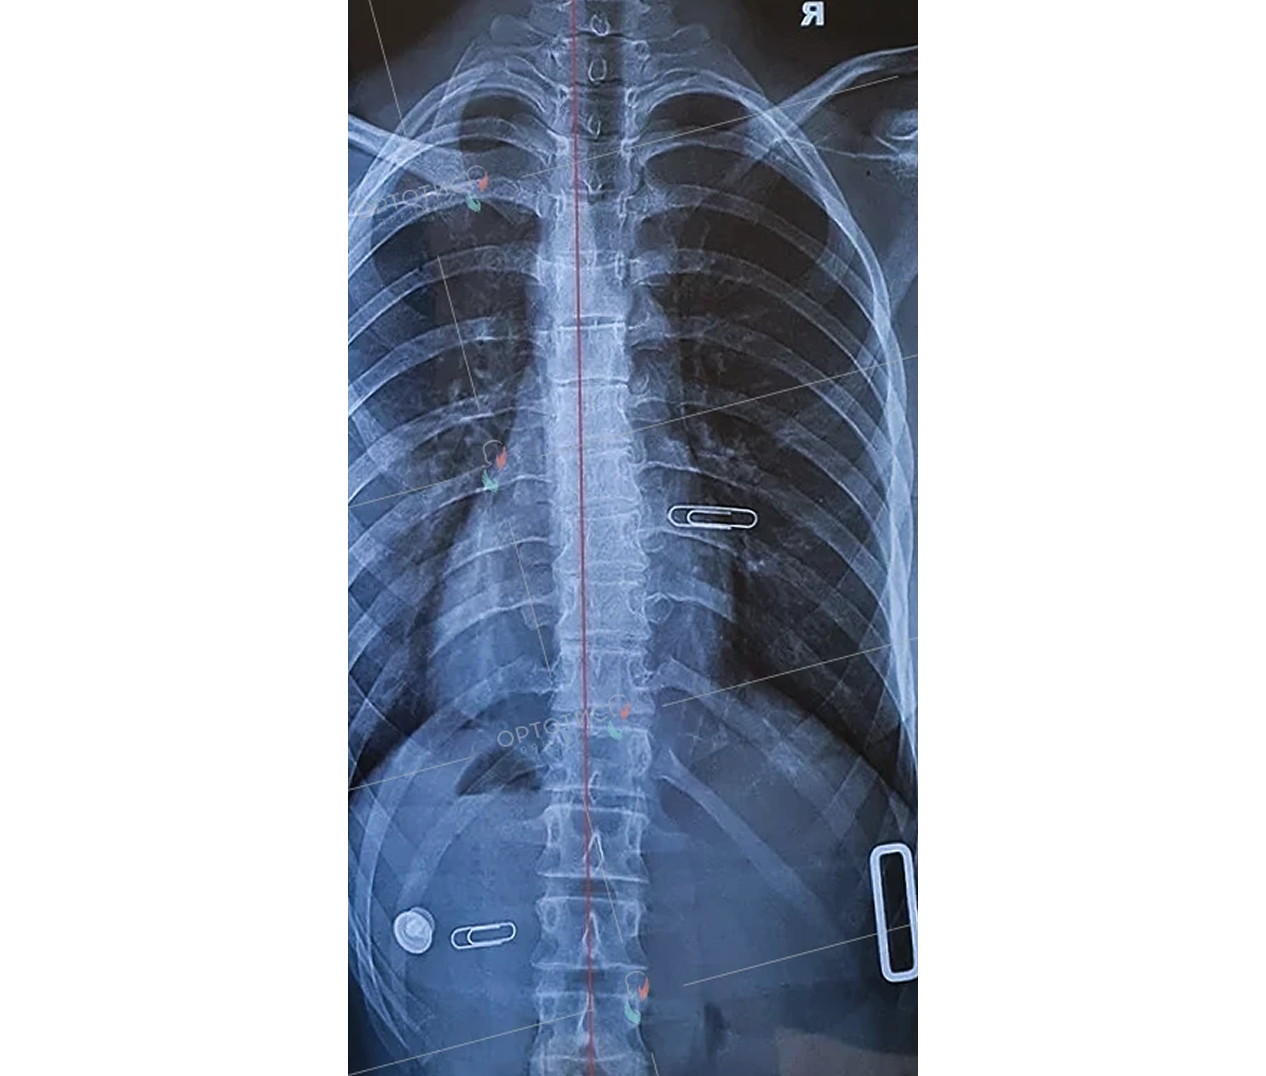

Корсет Шено — это «золотой стандарт» в лечении сколиоза у детей и подростков. В клинике Ортотис Центральная Азия в Алматы мы изготавливаем активные ортопедические корсеты, которые не просто удерживают позвоночник, а эффективно исправляют деформацию.

• Идиопатический сколиоз с углом искривления от 20° по Коббу;

Мы используем высокоточное 3D-моделирование, что позволяет создать корсет, идеально соответствующий анатомии ребенка. Это обеспечивает максимальную коррекцию при сохранении мобильности. Наши техники-ортопеды в Алматы проводят регулярную коррекцию изделия по мере исправления позвоночника.